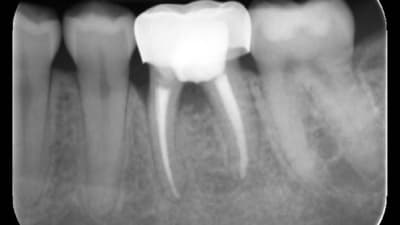

Products in Practice Restorative Digital Workflow Across Multiple Practices Achieves Efficient and Esthetic Results By Laura Justice, DMD June 01, 2020 13 min read